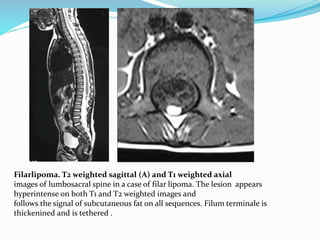

Filarlipoma. T2 weighted sagittal (A) and T1 weighted axial

images of lumbosacral spine in a case of filar lipoma. The lesion appears

hyperintense on both T1 and T2 weighted images and

follows the signal of subcutaneous fat on all sequences. Filum terminale is

thickenined and is tethered .